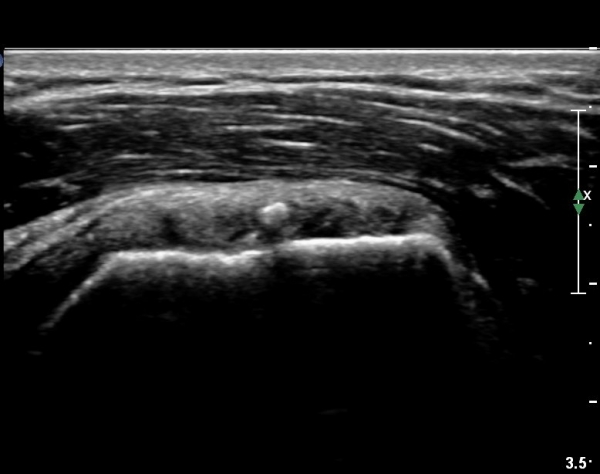

°ß°©ÇÏ±Ù°Ç ÁߺΠÁ¾´Ü¸é°Ë»ç¿¡¼­ ƯÀÌ ¼Ò°ßÀ» º¸ÀÌÁö ¾ÊÀ¸³ª(»çÁø 2) ŽÃËÀÚ¸¦ Á¶±Ý ÇϹæ(´Ù¸®ÂÊ)

À¸·Î À̵¿ÇÏ´Ï °ß°©Çϱٰdz»  ¼®È¸È­ µ¢¾î¸®°¡ °üÂûµÈ´Ù(»çÁø 3).